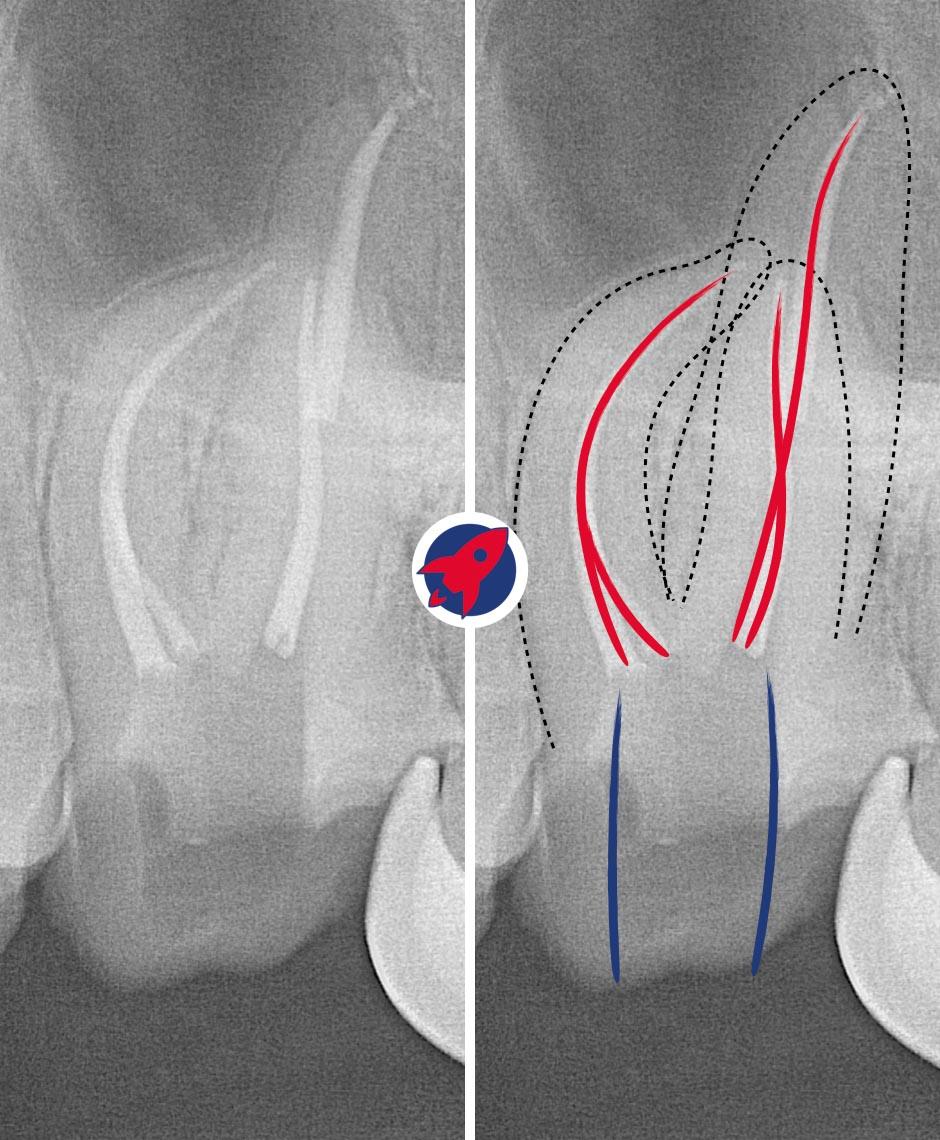

Preserve before replacing.

Rotary instrumentation, chemical disinfection, and microscopy with a clear plan for definitive restoration.